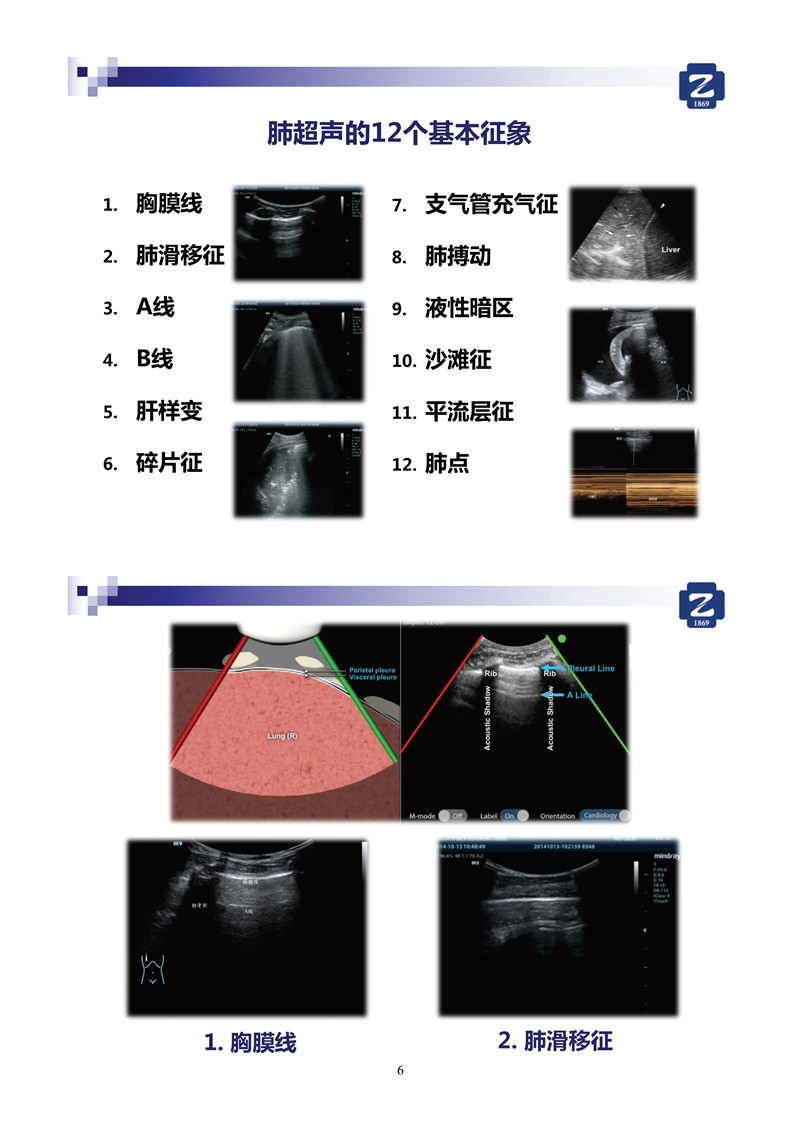

第二版新型冠狀病毒肺炎超聲診斷實用手冊_2.jpg